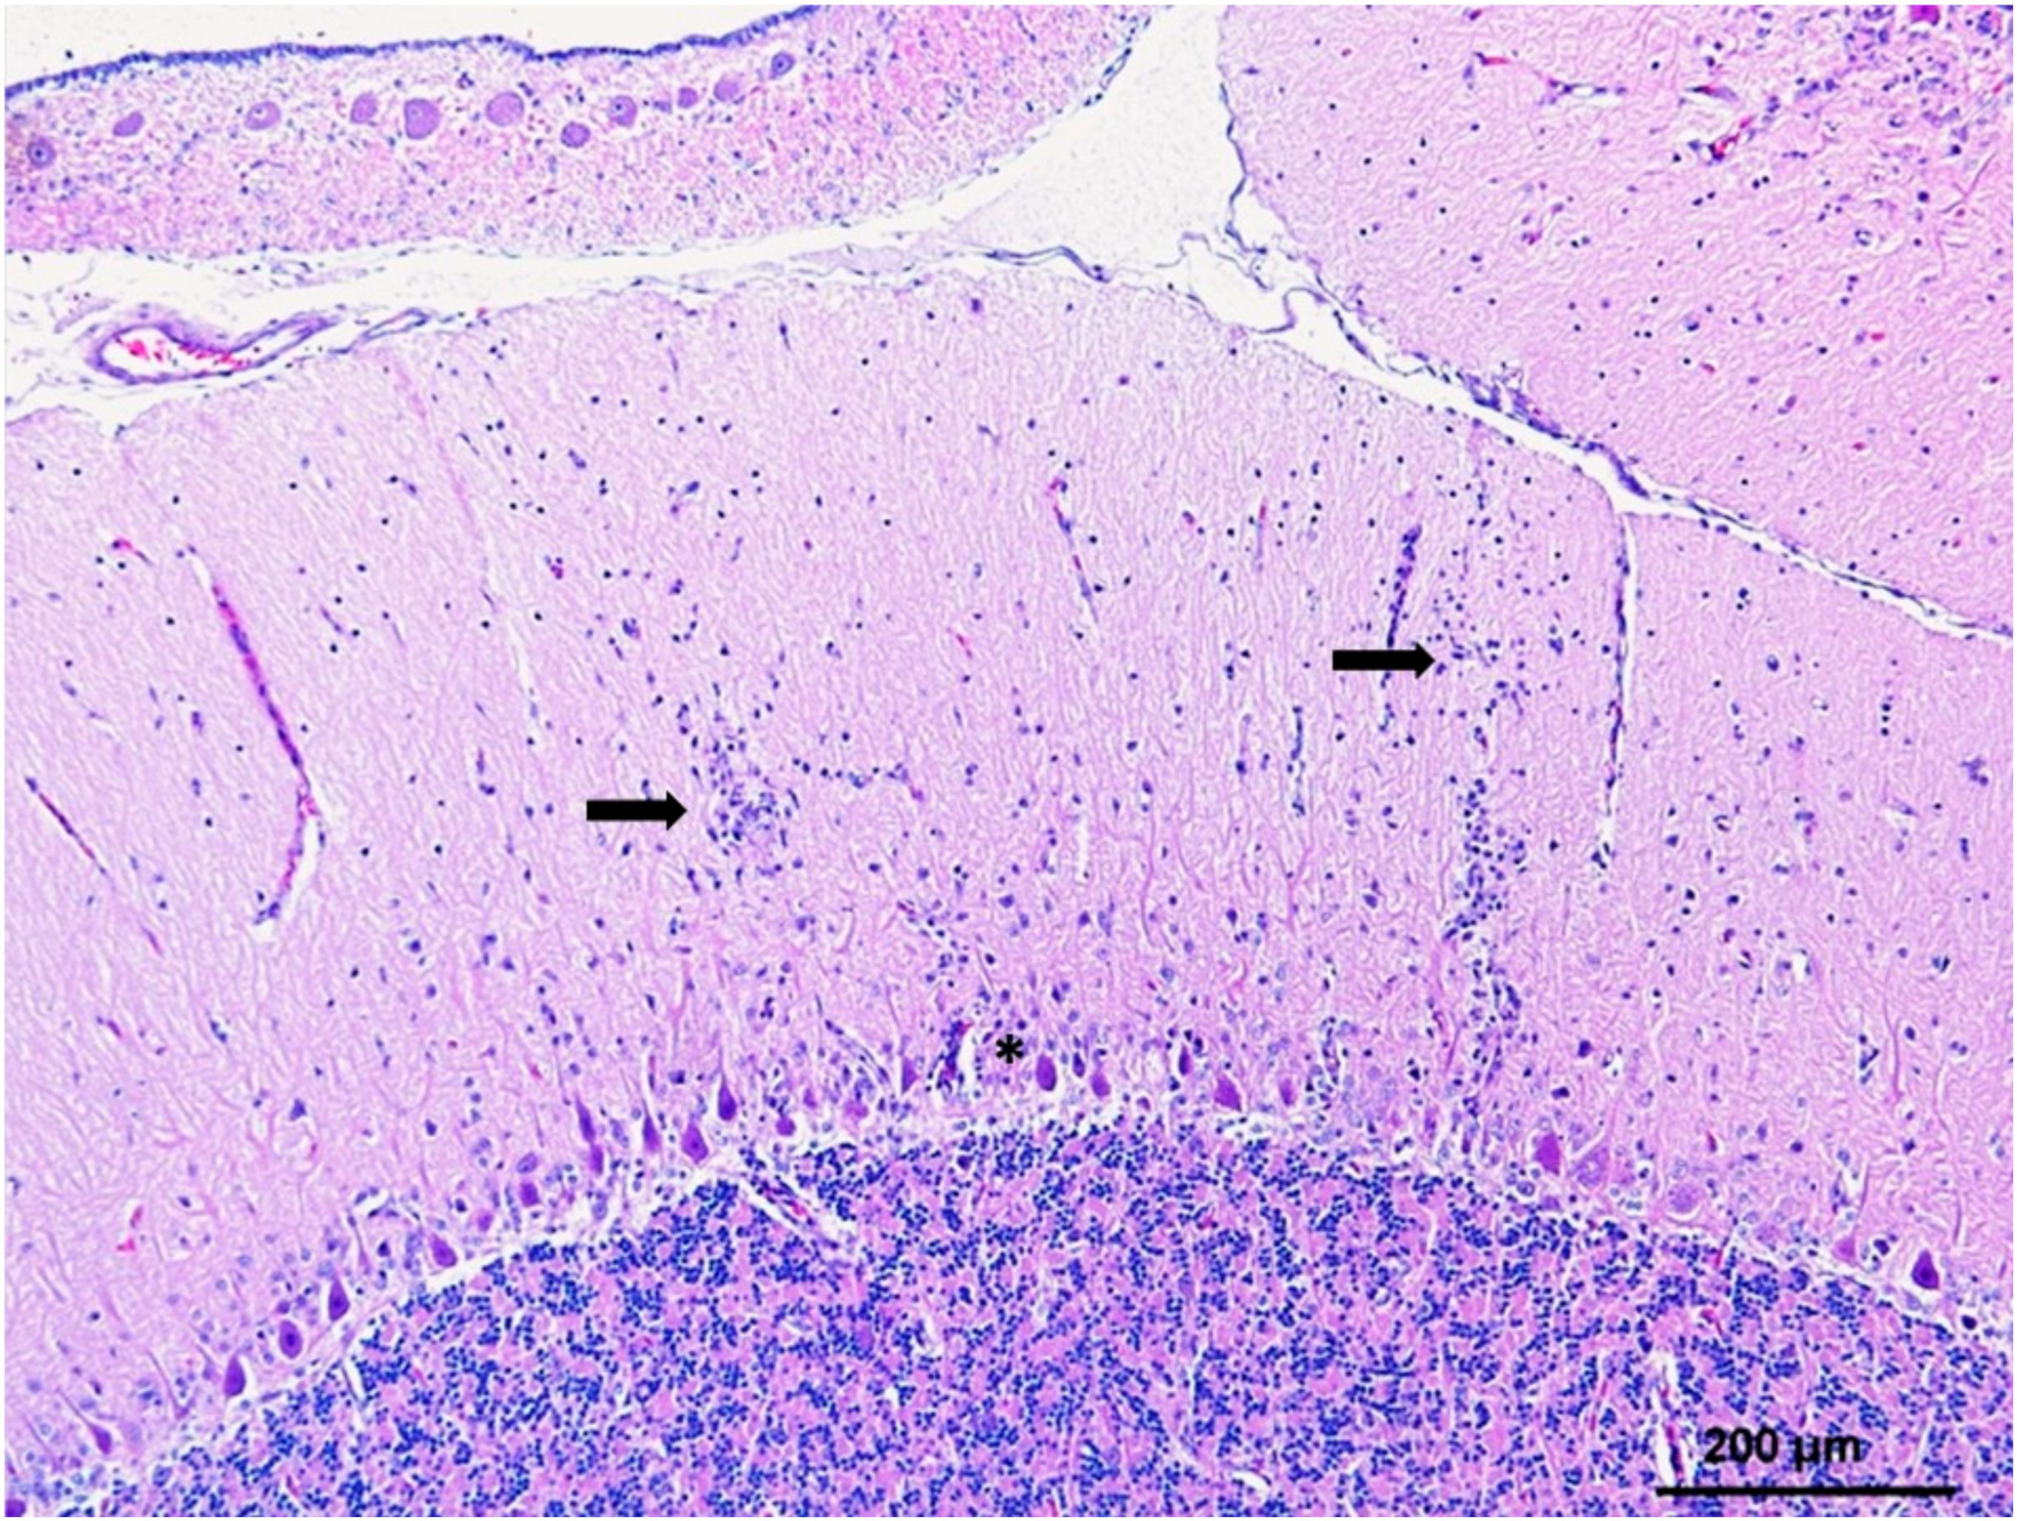

5.2. CNS and Eye

- Feyer, S.; Bartenschlager, F.; Bertram, C.A.; Ziegler, U.; Fast, C.; Klopfleisch, R.; Muller, K. Clinical, pathological and virological aspects of fatal West Nile virus infections in ten free-ranging goshawks (Accipiter gentilis) in Germany. Transbound. Emerg. Dis. 2020. [Google Scholar] [CrossRef]

- Erdelyi, K.; Ursu, K.; Ferenczi, E.; Szeredi, L.; Ratz, F.; Skare, J.; Bakonyi, T. Clinical and pathologic features of lineage 2 West Nile virus infections in birds of prey in Hungary. Vector Borne Zoonotic Dis. 2007, 7, 181–188. [Google Scholar] [CrossRef] [PubMed]

- Gamino, V.; Hofle, U. Pathology and tissue tropism of natural West Nile virus infection in birds: A review. Vet. Res. 2013, 44, 39. [Google Scholar] [CrossRef]